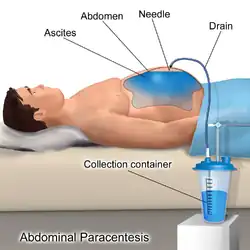

Paracentesis (from Greek κεντάω, "to pierce") is a form of body fluid sampling procedure, generally referring to peritoneocentesis (also called laparocentesis or abdominal paracentesis) in which the peritoneal cavity is punctured by a needle to sample peritoneal fluid.[1][2]

The procedure is used to remove fluid from the peritoneal cavity, particularly if this cannot be achieved with medication. The most common indication is ascites that has developed in people with cirrhosis.

The patient is requested to urinate before the procedure; alternately, a Foley catheter is used to empty the bladder. The patient is positioned in the bed with the head elevated at 45–60 degrees to allow fluid to accumulate in lower abdomen. After cleaning the side of the abdomen with an antiseptic solution, the physician numbs a small area of skin and inserts a large-bore needle with a plastic sheath 2 to 5 cm (1 to 2 in) in length to reach the peritoneal (ascitic) fluid. The needle is removed, leaving the plastic sheath to allow drainage of the fluid. The fluid is drained by gravity, a syringe, or by connection to a vacuum bottle. Several litres of fluid may be drained during the procedure; however, if more than two litres are to be drained, it will usually be done over the course of several treatments.[6] After the desired level of drainage is complete, the plastic sheath is removed and the puncture site bandaged.[6] The plastic sheath can be left in place with a flow control valve and protective dressing if further treatments are expected to be necessary.[6]